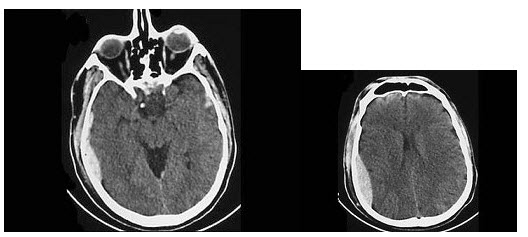

18、多项选择题

21、多项选择题

男,57岁,睡觉打鼾,近来加重,CT扫描如图所示,正确的描述或诊断是()

A.鼻咽腔偏右侧可见类圆形软组织块影

B.肿块内密度尚均匀,其上方见较多钙化影

C.肿块边缘大部清楚,邻近结构未见明显受侵

D.鼻咽癌

E.鼻咽部多形性腺瘤